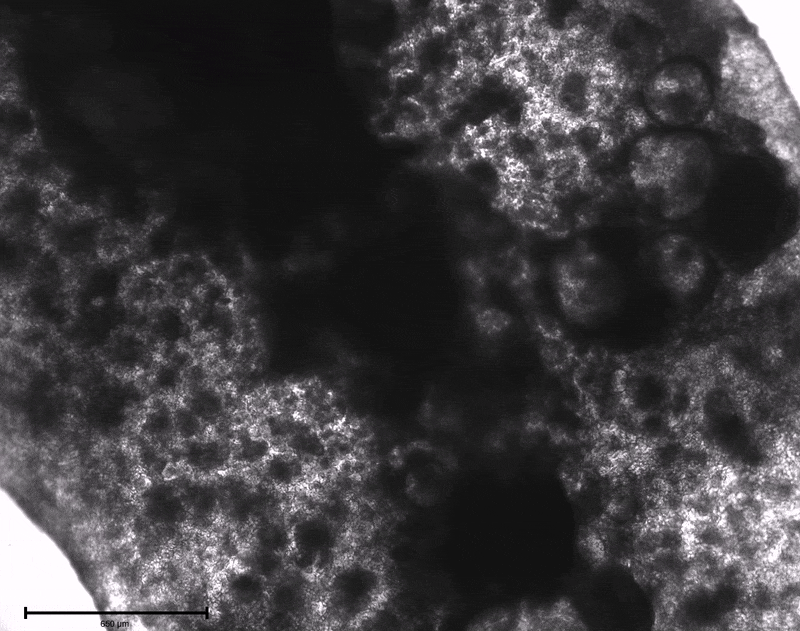

A Breakthrough with Beating 3D Cardiac Tissues

Using LunaGel™, Dr. Pioner’s team was able to encapsulate iPSCs directly within a 3D strip, guiding them through cardiac differentiation. Within just 7 days, the constructs began to beat spontaneously, a clear indication that the iPSCs had successfully matured into functional cardiomyocytes within the matrix.

This result not only validated their approach but also opened the door to scaling up their tissue production for broader experimental use, potentially reducing time and resource constraints often associated with sourcing mature iPSC-cardiomyocytes.